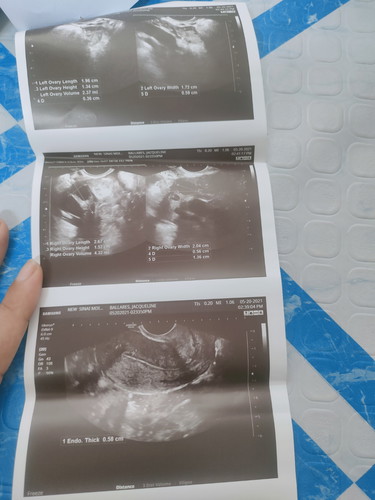

Done Check up..2 times na akong ngpatranvi.And for the second may follicle daw right Side Ng ovary .

Done Check up..2 times na akong ngpatranvi.And for the second may follicle daw right Side Ng ovary . ##1stimemom #firstbaby #pregnancy #pleasehelp